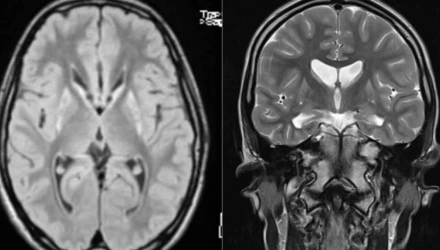

Η νόσος του Χάντινγκτον είναι μια σπάνια νευροεκφυλιστική ασθένεια που επηρεάζει την υγεία περίπου 5 ατόμων ανά 100.000 πληθυσμού. Προκαλεί προοδευτική καταστροφή των νευρικών κυττάρων του εγκεφάλου, με αποτέλεσμα να επηρεάζει:

Τα συμπτώματα εμφανίζονται συνήθως στην ηλικία των 30-50 ετών και επιδεινώνονται σταδιακά με την πάροδο του χρόνου.

Η νόσος προκαλείται από μετάλλαξη στο γονίδιο HTT, το οποίο είναι υπεύθυνο για την παραγωγή της πρωτεΐνης huntingtin. Αν ο ένας γονέας φέρει τη μετάλλαξη, κάθε παιδί έχει 50% πιθανότητα να την κληρονομήσει.